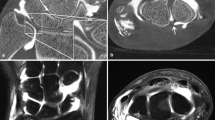

Axial images of advanced joint phantoms tibial epiphyses of cadaveric pig knees mounted in a bi-hemispheric plastic model filled with iodinated contrast agent (in this example, at an iodine concentration of 45 mg/ml). Joint phantoms were scanned in flat panel CT (FPCT; a, 5-s,b 8-s, and c 20-s runs) and d multidetector (MDCT). Note increasing image quality and depictability of anatomical structures with decreasing image noise from the 5-s to the 20-s FPCT run (a–c). Also, note the similar noise levels of the FPCT 5-s run (a) and MDCT (d)

First, axial images of advanced joint phantoms were produced. Therefore, FPCT images were postprocessed by reconstructing axial thin-slice images with a 10-cm volume-of-interest employing a high frequency/bone kernel. Matrix size of reconstructed images was 512 × 512 × 512. This resulted in isotropic voxels of 0.29-mm edge length. MDCT images were also postprocessed by reconstructing axial images at 10-cm field-of-view and 512 × 512 matrix size. Slice thickness was 0.75 mm, and the increment was 0.4 mm.

For human cadaveric joints, multiplanar reformations (MPR) were calculated from raw data in coronal, sagittal, and axial planes for both FPCT and MDCT. Slice thickness and increment were identical (1 mm and 0.6 mm respectively; Figs. 2, 3).